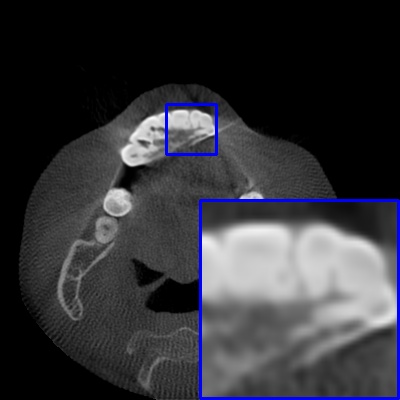

Figure 3: Visual comparison of MAR images by different methods on synthetic MA image. The PSNR (dB)/SSIM results are reported below each image for reference.

Results on synthetic MAR. In Table 1, we provide the quantitative results. One can see that our MARformer-L outperforms the other methods in terms of PSNR and SSIM, but needs only 11.76M parameters and 60.25G FLOPs. Note that the second best method Uformer-B has 50.42M parameters and 205.82G FLOPs. Besides, our MARformer-T achieves similar PSNR and SSIM results with Uformer-T, but needs only 0.40M parameters and 12.82G FLOPs compared to 5.24M and 25.39G for Uformer-T. Our MARformers also achieves faster inference speeds than the Uformers, though with inferior Dice scores, respectively. The qualitative results of visual quality are presented in Fig. 3. We observe that our MARformer-L well recovers the teeth shapes and obtains higher PSNR and SSIM results than the other comparison methods. The light-weight MARformer-L achieves similar results to Uformer-T. All these results validate that our MARformer is more efficient than the comparison methods on dental CBCT MAR.